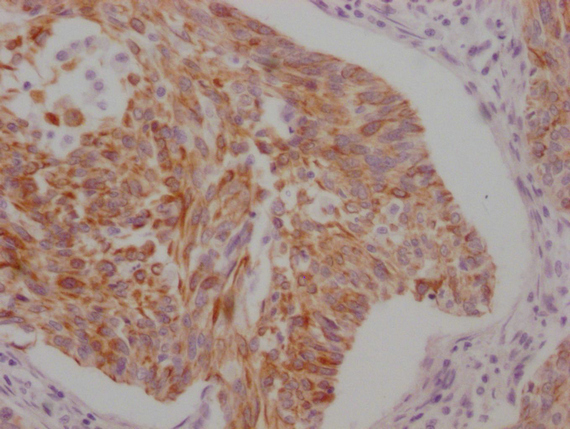

IHC image of MACO0502 diluted at 1:100 and staining in paraffin-embedded human cervical cancer performed on a Leica BondTM system. After dewaxing and hydration, antigen retrieval was mediated by high pressure in a citrate buffer (pH 6.0). Section was blocked with 10% normal goat serum 30min at RT. Then primary antibody (1% BSA) was incubated at 4°C overnight. The primary is detected by a Goat anti-mouse IgG polymer labeled by HRP and visualized using 0.05% DAB.